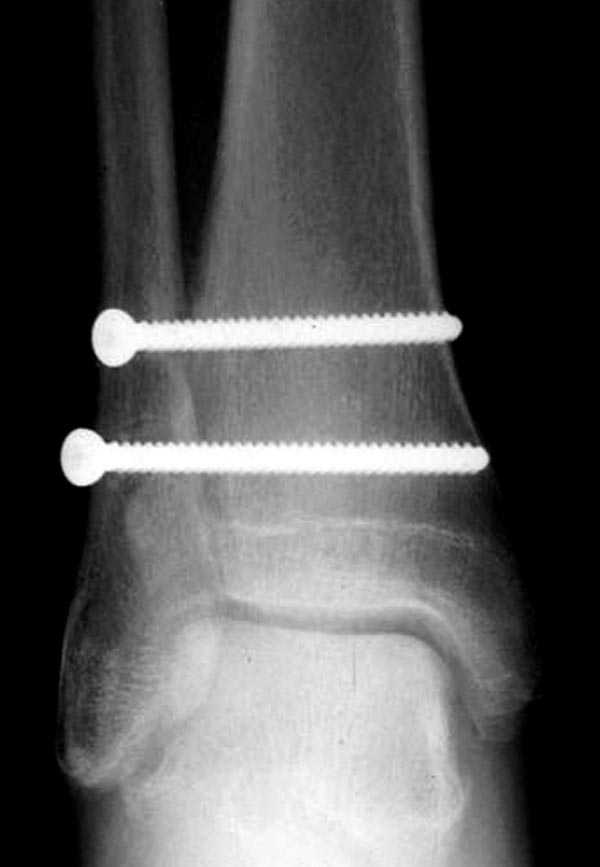

Невозможно устранить проблему фиксацией малоберцовой пластиной или другими методами, потому что главная проблема - разрыв межберцовой мембраны, которая находится между костями и внизу в голеностопе в синдесмозе.

Две параллельных шурупа создают условия для сращения мембраны и синдесмоза, 8 недельный срок достаточен, и можно удалить фиксаторы.